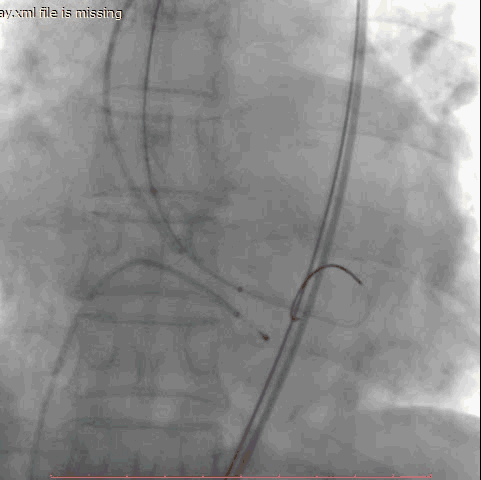

第一例手术的患者是一位86岁男性,间断胸闷症状2月,入院后超声提示主动脉瓣重度狭窄并少中量反流,平均跨瓣压差60mmHg,收缩期峰值流速4.9m/s,最大压差96mmHg。术前CT评估主动脉瓣环22.6*28.5mm,周长80.2mm,面积498.8mm2,右侧股动脉为主入路,应用24mm微创心通敖广球囊预扩张,植入27mm微创心通Vifaflow瓣膜,术后造影提示无瓣周漏,超声提示主动脉瓣跨瓣无压差。

术前影像